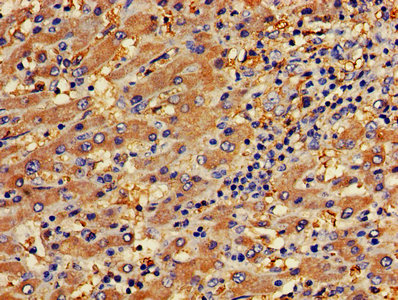

IHC image of CSB-PA017767LA01HU diluted at 1:400 and staining in paraffin-embedded human liver cancer performed on a Leica BondTM system. After dewaxing and hydration, antigen retrieval was mediated by high pressure in a citrate buffer (pH 6.0). Section was blocked with 10% normal goat serum 30min at RT. Then primary antibody (1% BSA) was incubated at 4°C overnight. The primary is detected by a biotinylated secondary antibody and visualized using an HRP conjugated SP system.